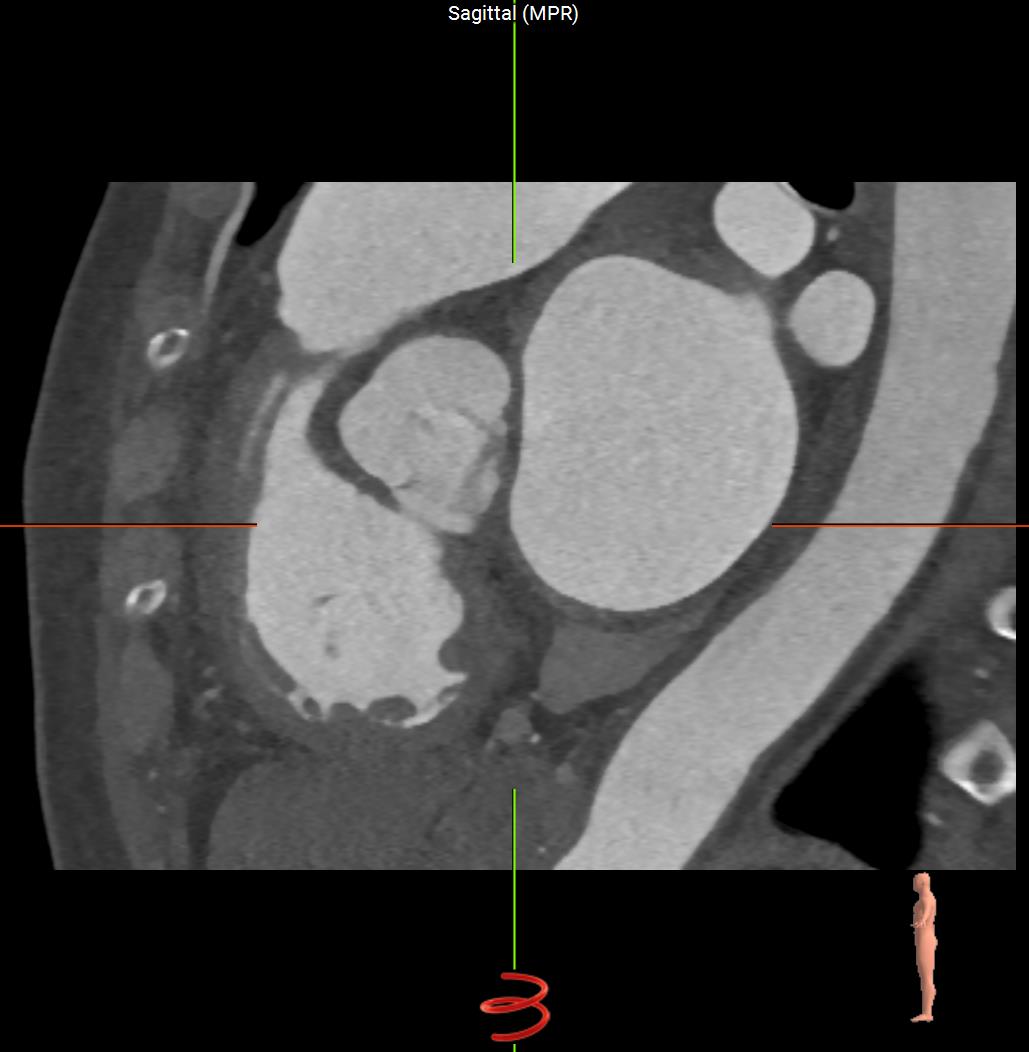

Sagittal-CT-Heart.jpgCoronal-CT-Heart.jpgAxial-CT-Heart.jpg